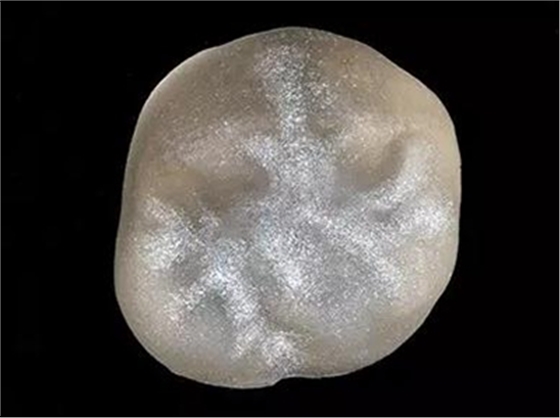

步驟12

最終修復(fù)冠

拋光后的修復(fù)冠。由VITA SUPRINITY材料制作, 選擇1M2-HT。